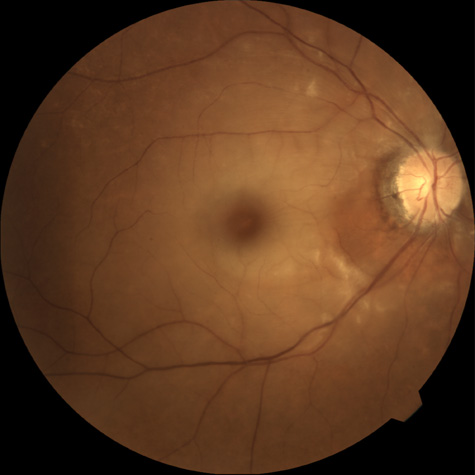

The clinical picture is typically striking. Patients present with a sudden painless loss of vision. The appearance of a cherry-red spot in the fundus is characteristic (Fig. 1).2 The cherry-red spot appears because soon after obstruction of the blood flow to the inner retina, the normally transparent retina becomes opaque and blocks the brownish-red color from the underlying choroid, which is still supplied by blood. Because the retina overlying the foveola is relatively thin, however, the normal color of the choroid is still visible in this area.3,4 Although characteristic, the cherry-red spot is not pathognomonic for central retina artery obstruction.5 Sometimes the characteristic cherry-red spot does not develop; there may be only a slight accentuation of the brownish-red color in the foveola.4 It is not known how long it takes this cherry-red spot to appear, but in a primate model, it has appeared as early as 30 minutes after obstruction.6 An afferent pupil defect is usually present.2

With time, the retinal opacity diminishes, generally leaving an optic nerve that is atrophic (Fig. 1). Frequently, thinned retinal arteries and veins also remain.7,8 No foveolar light reflex is evident, and a finely pigmented appearance of the macula is typical.7 In some cases, arterial collaterals develop at the optic disc.9–11 Rarely, anatomoses that exist between the central retinal artery and the ciliary arteries become visible as preretinal loops (Nettleship collaterals) after an occlusion at the edge of the disc.12,13,378In approximately 20% of patients, an embolus is evident somewhere in the arterial system.14 Emboli are discussed later.

Intravenous fluorescein angiography is useful in showing the details of the abnormal circulation of a central retinal artery obstruction (Fig. 1). The principal abnormality is the delay in the appearance of the dye in the central retinal artery and its branches.2 Rather than the central retinal artery and its branches filling rapidly, considerable time may elapse before the entire arterial system is filled.15 The filling of the retinal arteries is often abnormal, with the fluorescein partially filling an artery (a dye front) or hugging the vessel wall, as in normal venous filling.15

Optic coherence tomography (OCT) of an acute central retinal artery occlusion shows a slight increase in the thickening of the retina and reflectivity of the inner layers of the retina that correspond to the opacity seen clinically (Fig. 1).409 With time, the disc becomes atrophic and the retina thinner.